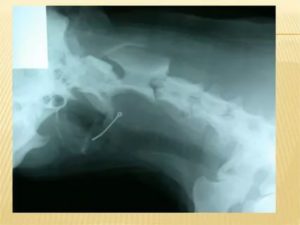

В большинстве случаев бывает сложно определить место локализации кости. Если она застряла между ротоглоткой и гортаноглоткой, то возникают не локальные, а разлитые болевые ощущения. Чтобы обнаружить кость в пищеводе, необходимо провести эндоскопическое исследование.